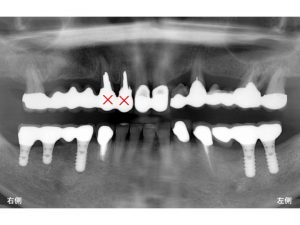

まず初診時のレントゲンから見てみましょう。

下顎の左右奥歯が欠損していました。

ただ、問題となっているのは下顎の左右の奥歯が欠損しているだけではありません。

神経のない歯が多く様々な問題を抱えていました。

以下の赤丸印は神経のない歯です。

●印の歯にはそれぞれ問題を抱えており、

治療の必要性がありましたが、

患者さんは下顎の欠損部のみの治療をご希望されました。

以下のバツ印は抜歯となりました。